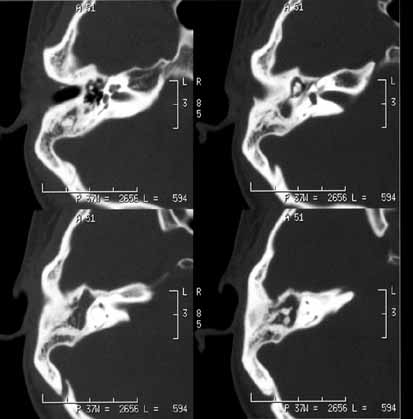

乳突炎02

女性,32岁,右耳反复脓性耳漏10年余。体检:右鼓膜大穿孔,鼓室有少许粘液性分泌物。

ct诊断:慢性乳突炎。